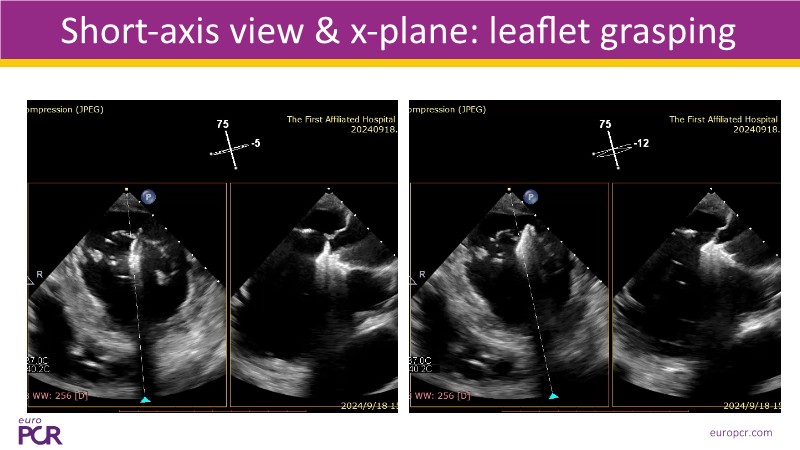

- To discover tips and techniques for mitral TEER in patients with challenging anatomy and difficult imaging